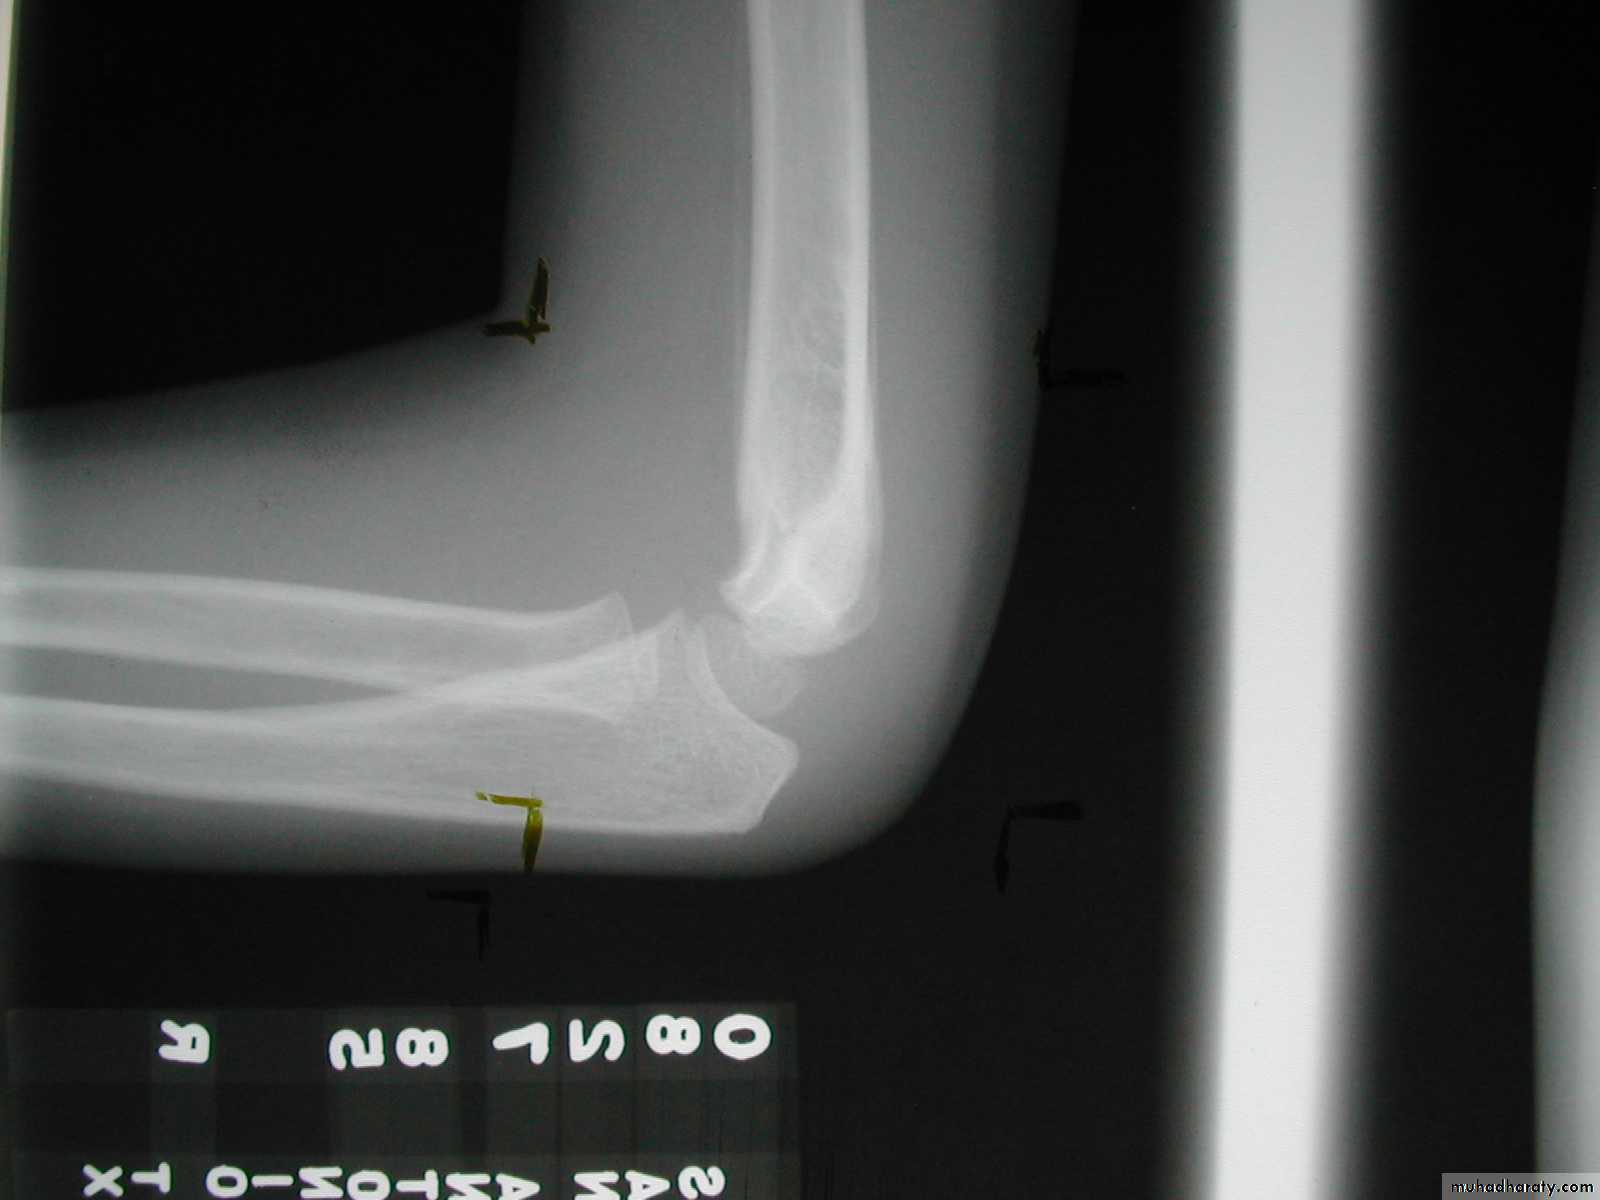

8 y.o.

Is this a simple extension

type supracondylar fracture ??

It also has

anterolatateraldisplacement !!

The distal fragment is

not flexed,but also it is not extended to any degree.

This also is a Type III Flexion Pattern.

What is differentabout this fracture?

But, if not recognized as such, it may be a problem.

This fracture was irreducible,

and required an open reduction !!!